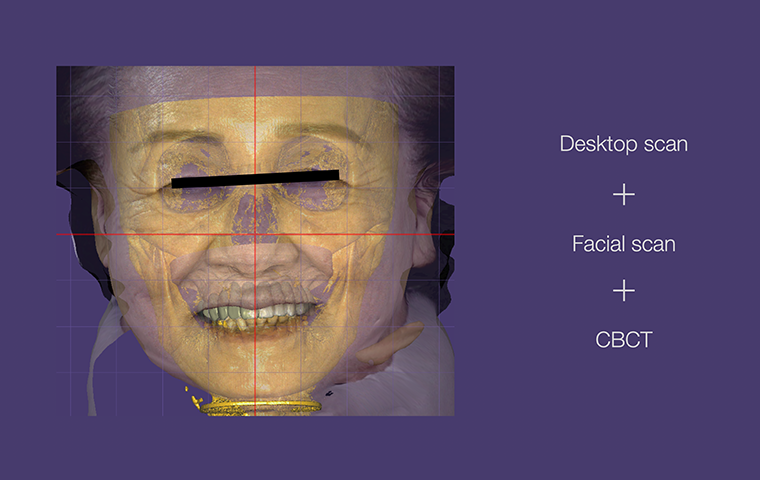

All-on-X

Practical Digital Prosthodontics: Understanding and applying

All-on-X treatment concept

Dr. Janghyun Paek

Professor at Kyunghee University, Department of Prosthodontics

All-on-X

Dr. Janghyun Paek

|

Practical Digital Prosthodontics: Understanding and Applying All-on-X Treatment Concept |

All-on-X

Dr. Janghyun Paek

|

Practical Digital Prosthodontics: Understanding and Applying All-on-X Treatment Concept |

Special Pre-Day Course

Practical Digital Minimalism

Dr. Janghyun Paek

Explore the digital implant dentistry, including the All-on-X treatment concept, guide surgery, immediate loading protocols, prosthodontic considerations, and soft tissue contouring. Course also includes hands-on for All-on-X implant placement, prosthodontic components, intraoral scan, and immediate loading.